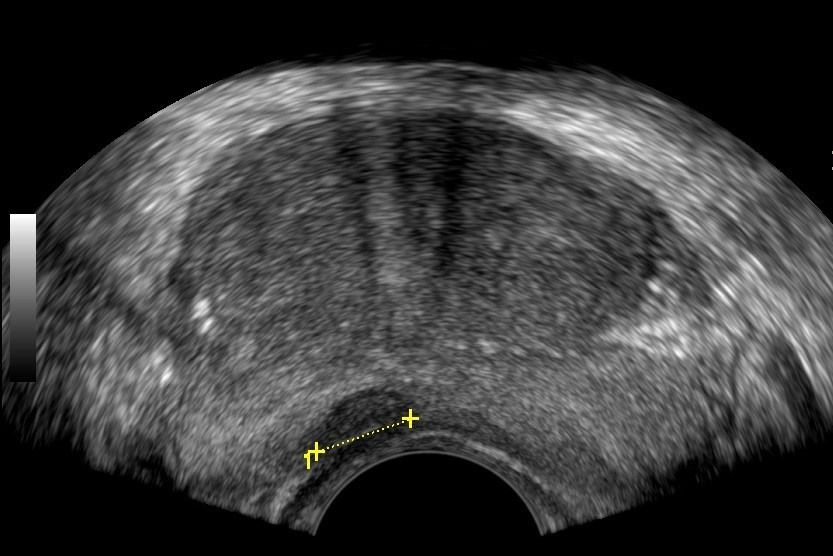

- Prostate: It allows for a detailed assessment of the prostate's morphology and size.

- Peripheral Prostate Zone: The exam can detect focal lesions, such as neoplasms, in the peripheral zone of the prostate.

- Central Prostate Zone: The central zone can be checked for the presence of inflammation, abscesses, calcifications, or other space-occupying lesions.

- Examination: The exam begins with a Lower Abdominal Ultrasound (suprapubic) and continues with the transrectal exam after urination. The transrectal ultrasound is performed using a special probe inserted into the rectum through the anal sphincter. This method provides a comprehensive evaluation of the prostate's morphology.